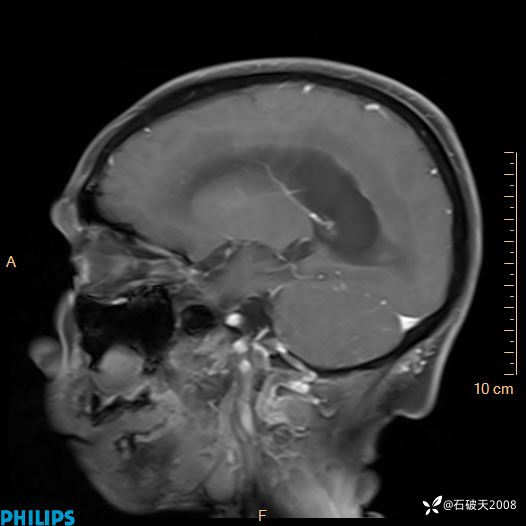

增强矢状位